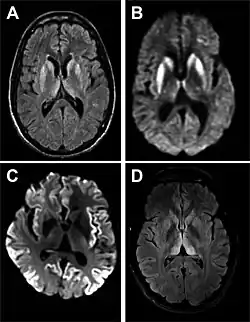

Magnetic resonance image of sporadic CJD[2]

Through the image of MRI, the obvious precipitation of prion protein in the brain is visible.

• MRI with diffusion weighted inversion (DWI) and fluid-attenuated inversion recovery (FLAIR) shows a high signal intensity in certain parts of the cortex (a cortical ribboning appearance), the basal ganglia, and the thalami.[42] The most common presenting patterns are simultaneous involvement of the cortex and striatum (60% of cases), cortical involvement without the striatum (30%), thalamus (21%), cerebellum (8%) and striatum without cortical involvement (7%). In populations with a rapidly progressive dementia (early in the disease process), MRI has a sensitivity of 91% and specificity of 97% for diagnosing CJD.[46] The MRI changes characteristic of CJD may also be seen in the immediate aftermath (hours after the event) of autoimmune encephalitis or focal seizures.[42]

Imaging of the brain may be performed during medical evaluation, both to rule out other causes and to obtain supportive evidence for diagnosis. Imaging findings are variable in their appearance and also variable in sensitivity and specificity.[49] While imaging plays a lesser role in diagnosis of CJD,[50] characteristic findings on brain MRI in some cases may precede onset of clinical manifestations.[51]

Brain MRI is the most useful imaging modality for changes related to CJD. Of the MRI sequences, diffuse-weighted imaging sequences are most sensitive.[52] Characteristic findings are as follows:

• Focal or diffuse diffusion-restriction involving the cerebral cortex or basal ganglia. The most characteristic and striking cortical abnormality has been called "cortical ribboning" or "cortical ribbon sign" due to hyperintensities resembling ribbons appearing in the cortex on MRI.[53] The involvement of the thalamus can be found in sCJD, is even stronger and constant in vCJD.[54]

• Varying degree of symmetric T2 hyperintense signal changes in the basal ganglia (i.e., caudate and putamen), and to a lesser extent globus pallidus and occipital cortex.[50]